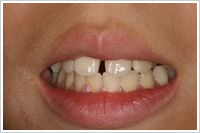

●4歳11か月

ず~と指しゃぶりをしている幼児

お母さんがどんなに注意をしてもやめません。手袋をして寝ても、寝ながら手袋をはずして指しゃぶりをします。指にわさびやからしをぬったら、夜中が大変。指に糸を巻きつけても駄目です。口が開いているので喉が弱く、よく風邪をひいたり、鼻炎になったりでお母さん(お父さんも)がたいへんでした。

●5歳5か月

指しゃぶり防止グローブをはめて約1週間で指しゃぷりをやめました。その後約6か月で、歯並びが正常になりました。 鼻炎もなくなりお医者さん通いが少なくなりました。何より顔つきがよくなりました。夜もぐっすり眠れるようになりました。これで治れば高額な矯正治療は必要ありません。